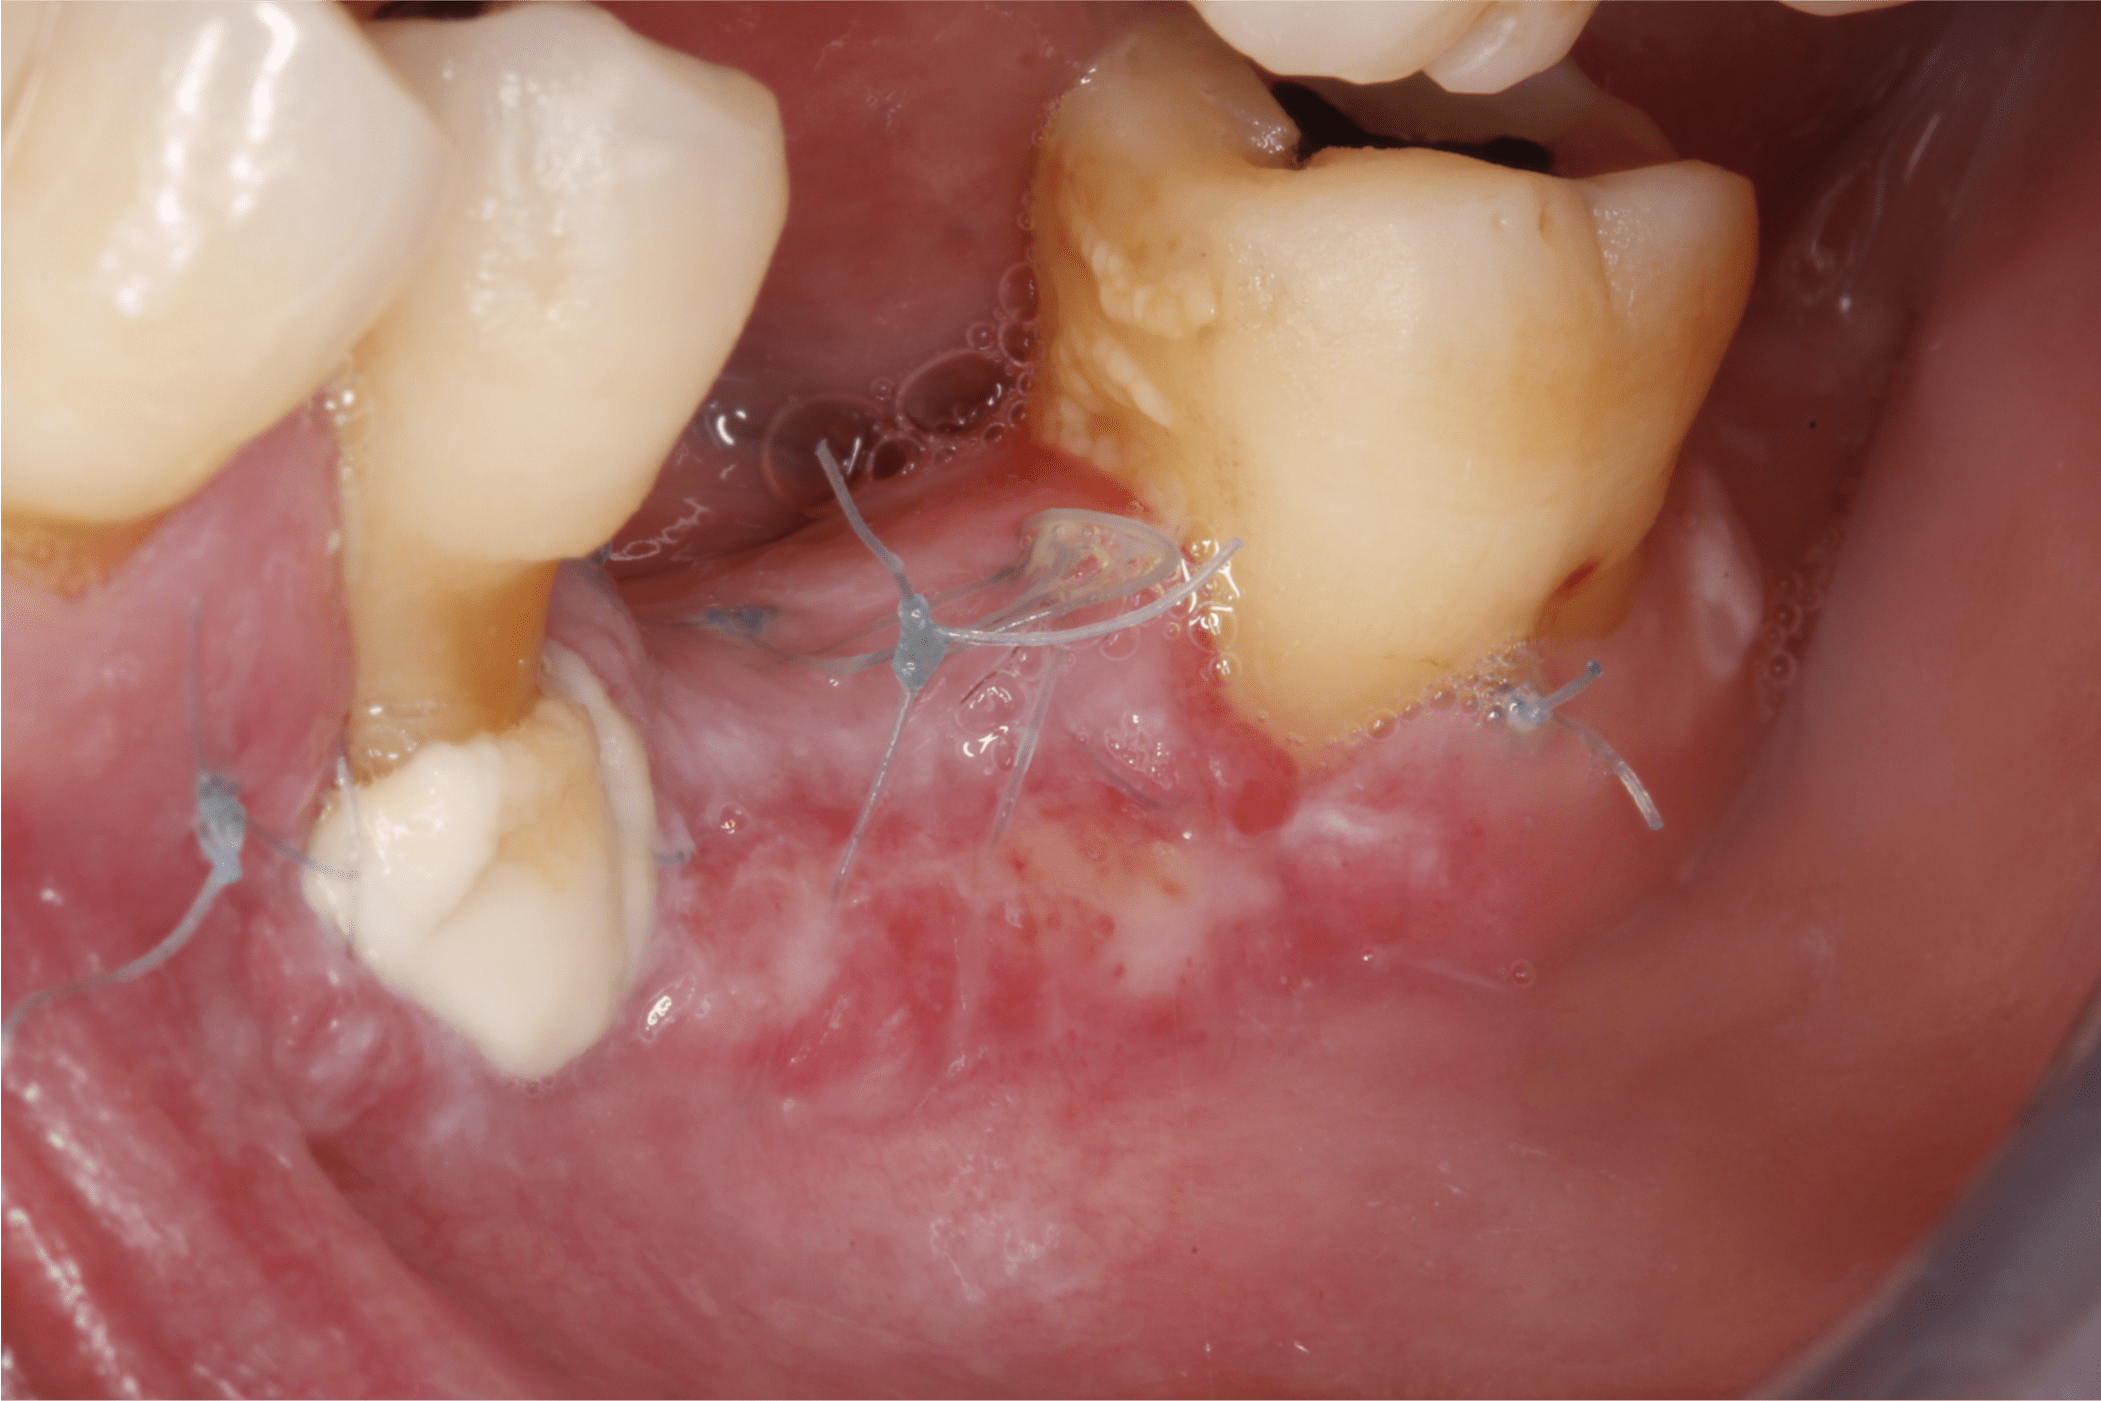

Una vez tomado el injerto epitelial se posicionó en el sitio receptor previamente preparado, se fijó con puntos simples en sus extremos y en la porción media se fijó con puntos colchoneros horizontal y cruzado (Fig. 9 y 10).

Fig. 9

Fig. 10